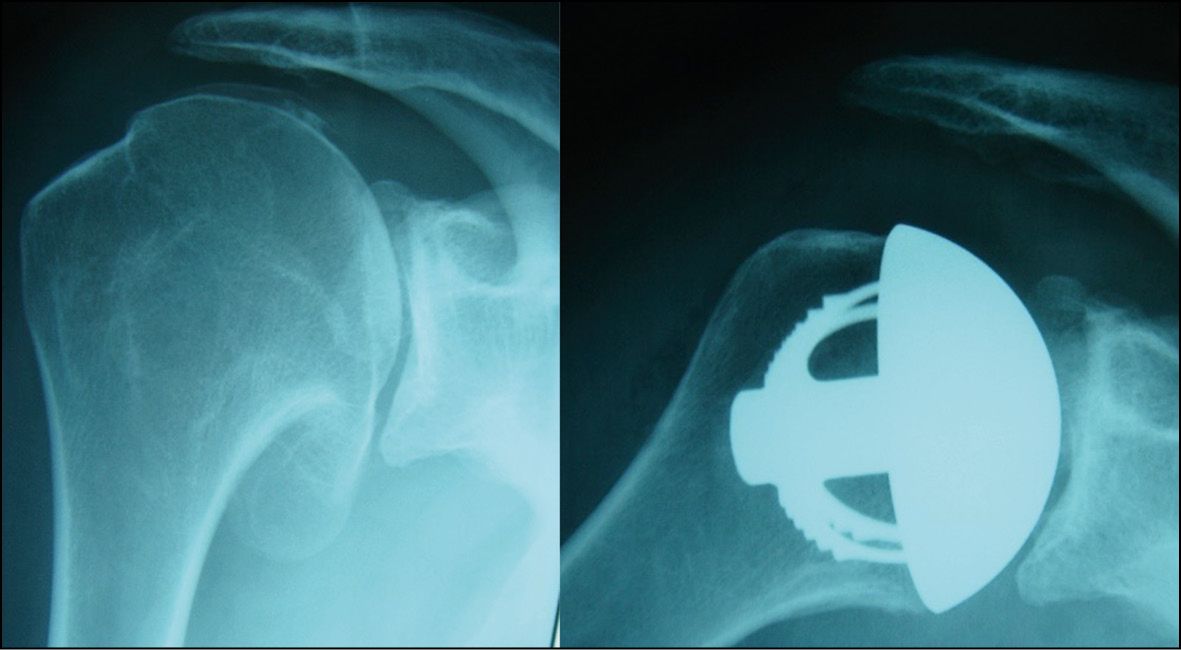

This issue's clinical contributions span alignment strategies and implant selection in major joint reconstruction. In total knee arthroplasty, one article examines TKA in extraarticular deformities managed through intraarticular correction without increased constraint, while a second introduces inverse kinematic alignment as a framework for personalized alignment. Shoulder arthroplasty is addressed through an assessment of the stemless shoulder implant. A further study evaluates whether surgical approach influences canal fill of the femoral component in THA, contributing to the evidence base on technique-dependent outcomes.